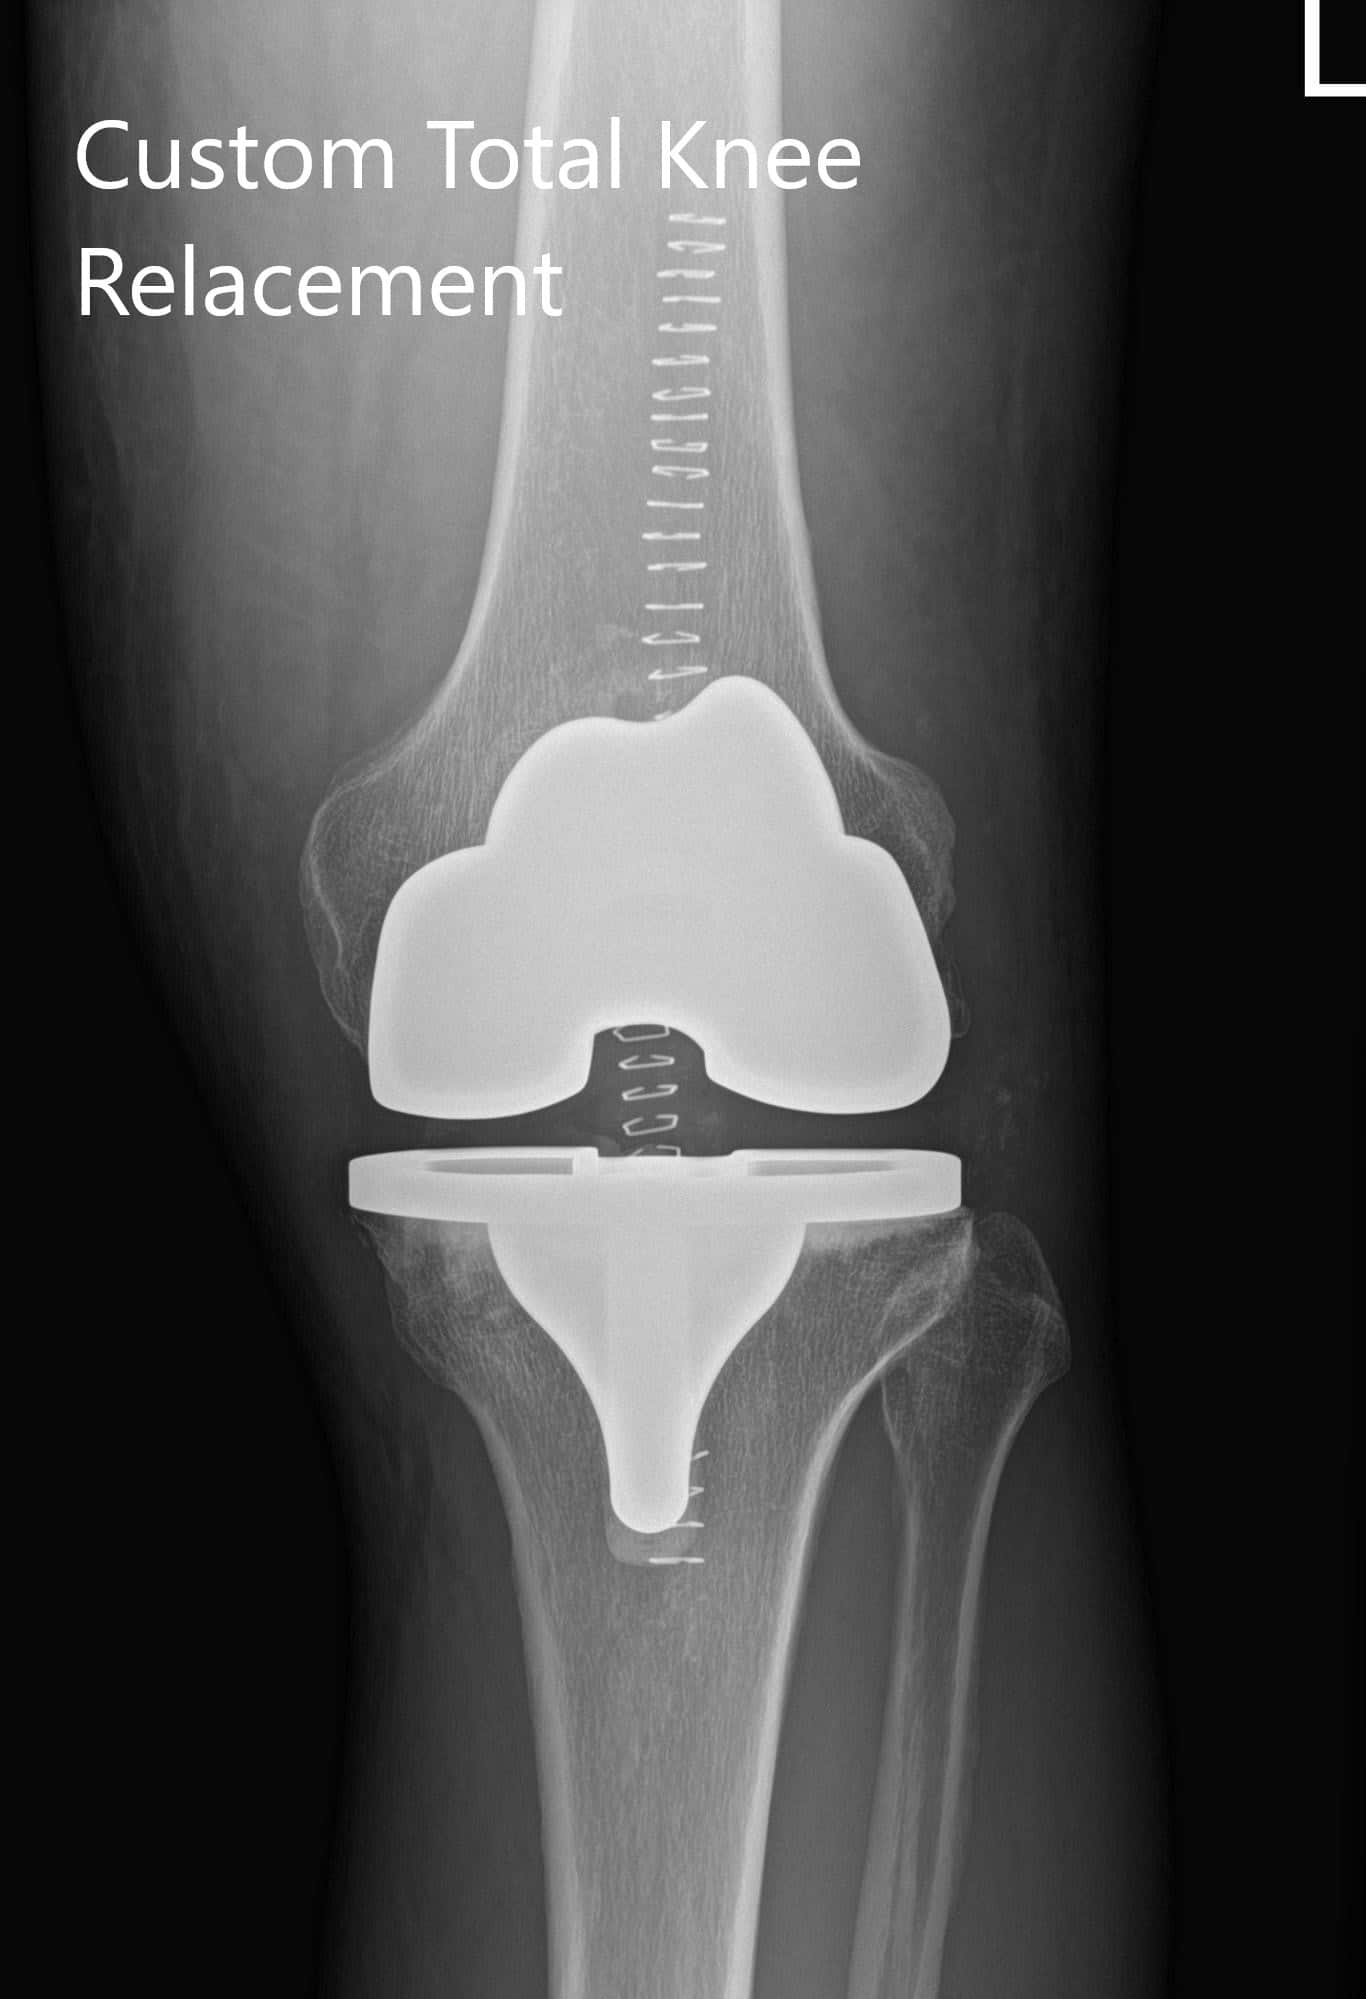

Preoperative X-ray of the left knee showing AP and lateral views

Preoperative X-ray of the left knee showing AP and lateral views.

Implant – Custom femur with a custom tibia and patella with 8-mm polyethylene insert.